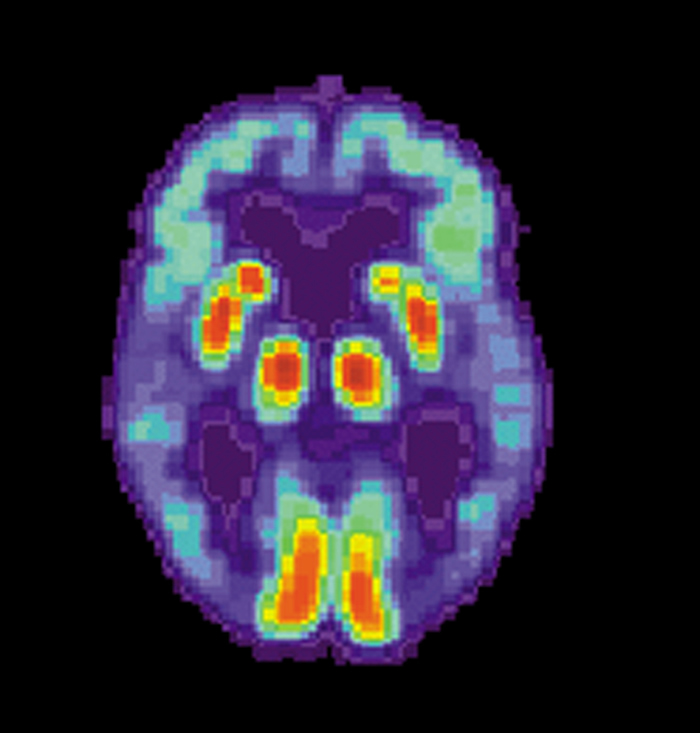

(蜘蛛网eeook.com报道)据EurekAlert!:载脂蛋白Eε4等位基因(这是晚发型阿尔茨海默病的主要遗传风险因子)的女性携带者会比男性罹患阿尔茨海默病的风险更大吗?《美国医学会杂志-神经内科学》上新发表的文章对这一问题进行了检查。

一个流行的观点是,携带载脂蛋白Eε4等位基因(APOE)拷贝的女性发生阿尔茨海默病的风险要比携带同样拷贝数该基因的男性更大。

南加州大学凯克医学院的Arthur W. Toga, Ph.D.和共同作者对27个研究报告进行了分析,这些研究数据包括了近5万8000名参与者,研究的目的是为了确定性别和APOE基因型是如何影响罹患轻微型认知损害(MCI)风险的,MCI常常是从正常认知老化向痴呆症及阿尔茨海默病演化的过渡状态。这些研究的参与者大多为白人,他们的年龄在55-85岁间。

在携带一个拷贝载脂蛋白Eε4等位基因的55-85岁的男女性中,他们在罹患阿尔茨海默病的风险上没有显示出差异,但在65-75岁的年龄段中,女性的患病风险似乎比男性有所增加。据分析结果披露,尽管在55-85岁年龄段中,男性和女性罹患MCI的风险没有差异,但在55-70岁年龄段间,女性的患病风险相比男性似乎有所增加。